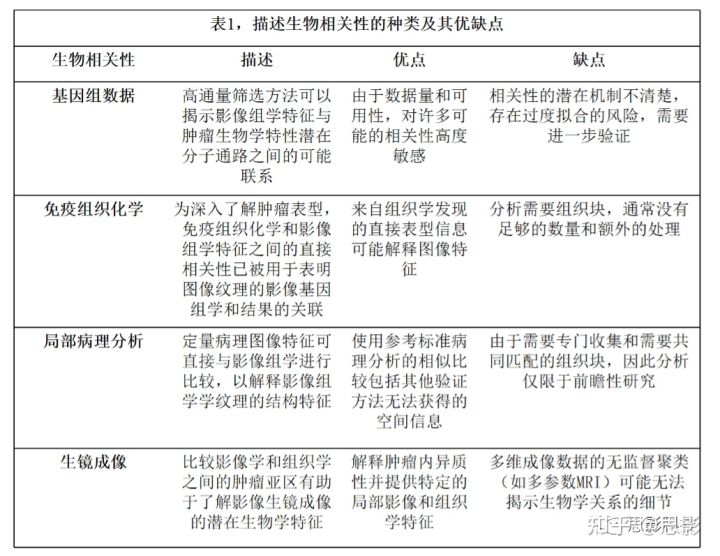

本文表明,最近研究在影像组学的生物学验证方面做出了重大努力。确定了迄今为止用于影像组学组学生物学基础的四类主要生物学相关性和方法,包括基因表达数据、免疫组织化学染色的蛋白质表达、微观组织结构和物理肿瘤生镜成像。

表1列出了这些核心内容及其评估的总结。